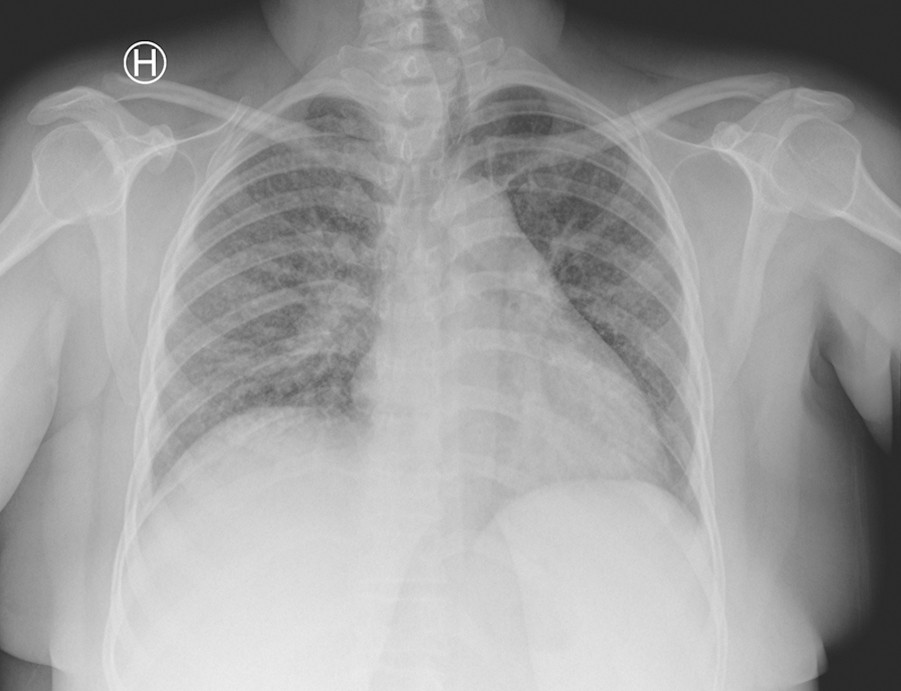

I to uker hadde hun så vekslende feber, svimmelhet og hodepine, etter hvert daglig oppkast, vedvarende tørrhoste og tung pust. Hun ble på nytt henvist til medisinsk avdeling ved lokalsykehuset. Ved innkomst (dag 1) var hun febril med temperatur 38,0 °C, blodtrykk 144/77 mm Hg, puls 101/min, respirasjonsfrekvens 16/min og O2-metning 98 %. CRP-nivået hadde steget til 130 mg/l. Røntgen thorax ved innleggelsen viste diffuse lungefortetninger bilateralt, oppfattet som mulig atypisk pneumoni (fig 1).

Diagnostisering av tilstanden hos gravide er som hos ikke-gravide basert på klinisk mistanke, sputumdiagnostikk samt røntgen thorax (1). Røntgen thorax utsetter ikke fosteret for målbar risiko og behøver ikke unngås dersom det foreligger indikasjon for undersøkelse.

Hos vår pasient ble diagnosen stilt etter rimelig tid, men gitt hennes opprinnelsesland og funn av bilaterale lungefortetninger, uten effekt av standard antibiotikabehandling, kunne behandlingen vært startet før. Særlig ved tuberkulose med affeksjon av sentralnervesystemet er rask behandling essensielt, og kvinnens helse bør gå foran forlengelse av svangerskapet når fosteret er levedyktig.